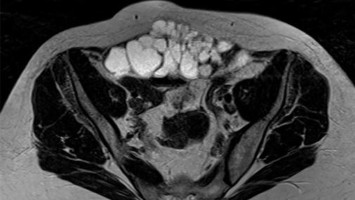

Was ist die Ursache für die Schmerzen im Unterbauch?

Ein 10-jähriges Mädchen in gutem Allgemeinzustand und altersentsprechender Entwicklung wurde aufgrund seit 4 Wochen bestehender und an Intensität zunehmender Unterbauchschmerzen zum Ausschluss eines entzündlichen Geschehens auf unsere Kinderstation aufgenommen. Mittels Bildgebung kamen die Ärzte der Ursache auf die Spur.